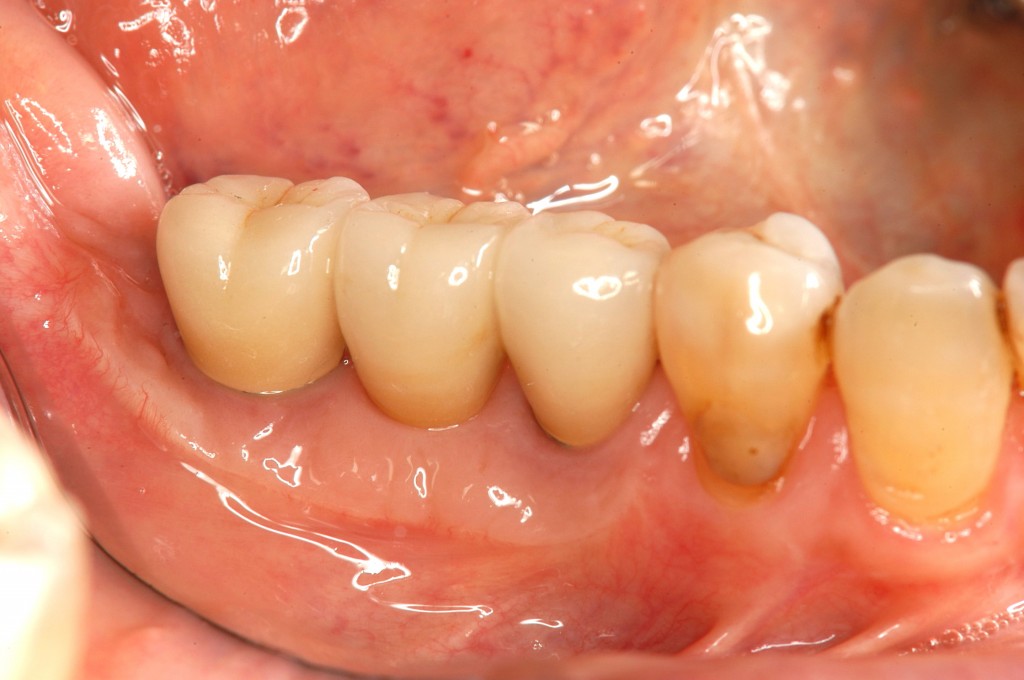

• 治療後

セラミックスで作った被せ物をつけて,完成です。

歯磨きがしやすい歯茎と,プラークの着きにくいセラミックスで,治療後のお手入れも簡単です。

見た目も綺麗になり,患者様には大変満足していただけました。